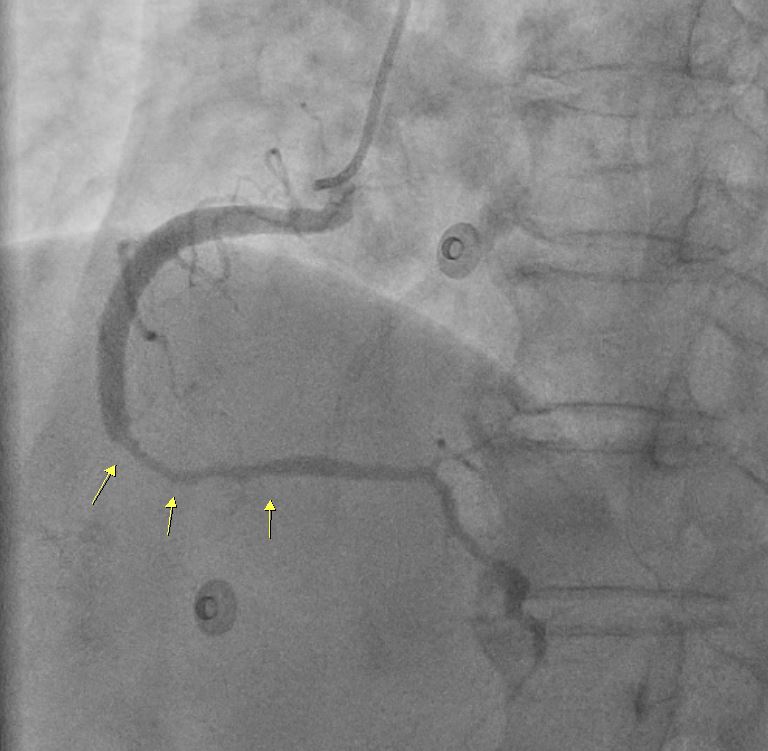

In the STEMI episode, in Dec, 2022, the LCX and RCA were patent. There were multiple odd stenotic lesions with in mid LAD, with some haziness suggested limited contrast filing. Six days after PCI, there was dissection flap, extending beyond previous angioplasty, with limited flow in LAD, compatible with the unstable ECG changes. In the NSTEMI episode, in Dec, 2022, the LAD was stationary without restenosis. But the RCA for new log lesion at segment 2 to segment 3.

1st PCI for STEMI 1. The odd LAD lesion was checked by IVUS,revealing coronary dissection in mid LAD. 2. Angioplasty was performed with a 2.75*10mm Wolverine cutting balloon up to 8A10¡±, with fair LAD flow. --2nd PCI for recheck and unstable ECG findings 1. For dissection flap extending to distal LAD, wiring with a Sion wire was performed carefully. 2. Check IVUS to confirm true-lumen wiring and the extension of the dissection. Intimal flap and large burden of sub-intimal hematoma were noted. 3. Angioplasty with a 2.0*20mm balloon catheter, but with poor distal flow. 4. Long stenting to mid-to-distal LAD according to IVUS findings, with Onyx 2.0*26mm and Onyx 2.5*30mm 5. Angioplasty with a 1.5*20mm balloon catheter for distal run-off, 4A10¡± 6. Post-stenting dilatation with a 2.5*10mm balloon catheter, 4A10", low pressure considering the sub-intimal hematoma 7. Check final IVUS: The stents were well apposed. The proximal sub-intimal hematoma was not fully covered due to the vessel-size discrepancy. 8. The final flow was fair --3rd PCI for NSTEMI 1. For the un-reasonable rapid progression of the RCA lesion, I checked IVUS and coronary dissection was noted again. 2. No PCI was performed thereafter due to acceptable blood flow. --4th cath half years later The LAD was stationary and the RCA lesion was totally resolved.